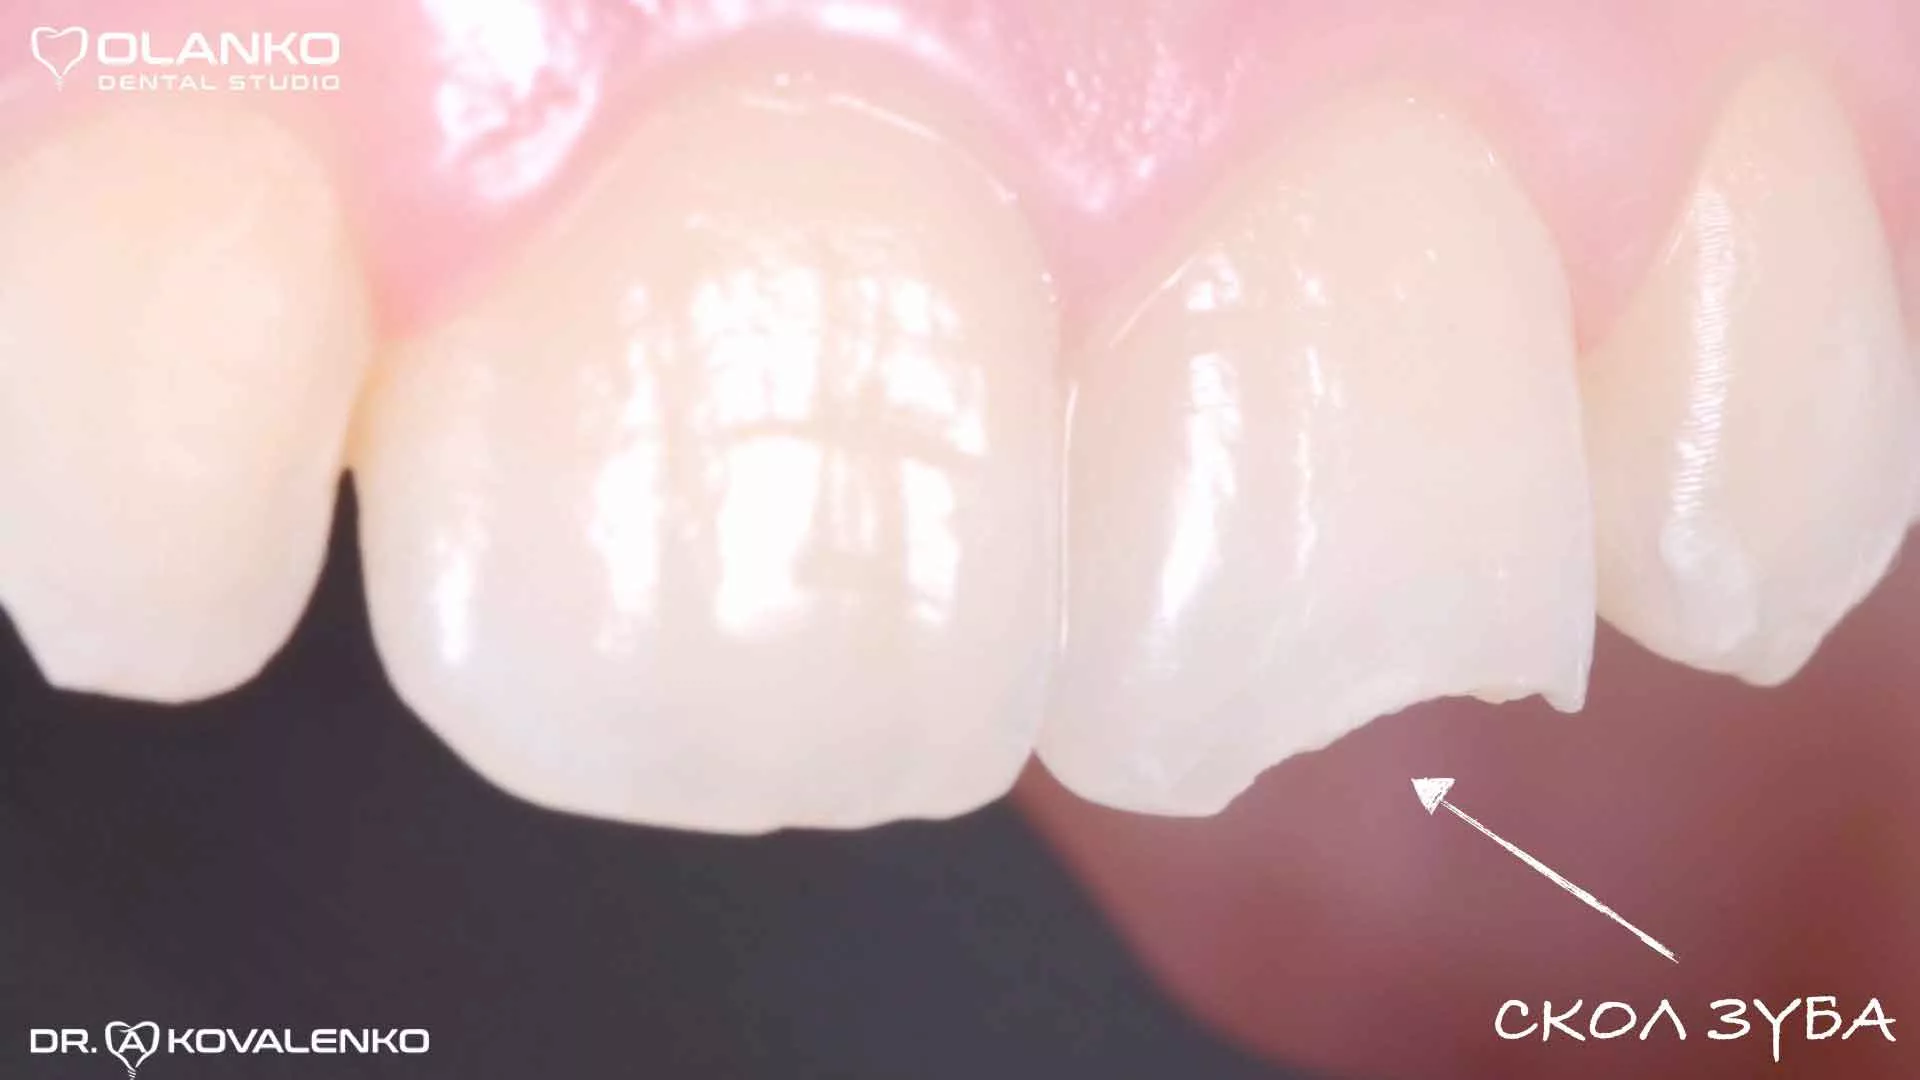

Фото переднього зуба зі сколом ріжучого краю

Реставрація фотополімером рекомендована пацієнтам з механічними травмами зуба та з іншими незначними відхиленнями від норми: